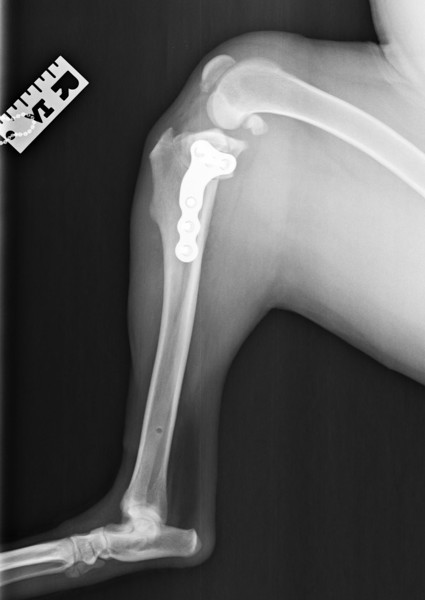

Dr. Maloney has a passion for and special training in surgery. She is experienced and adept at TPLO procedures for treatment of cranial cruciate ligament rupture, laryngeal lateralization for laryngeal paralysis, ventral bulla osteotomies for aural polyps in cats, as well as a wide variety of other soft tissue and orthopedic surgeries.